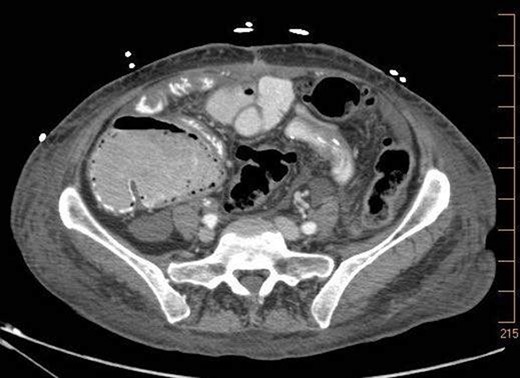

On 7.8.18 the patient had return of bowel function complicated by blood per rectum and an episode of bloody emesis with drop in Hgb 9 > 7.0. The patient received 2 units PRBCs. GI consulted deemed blood per rectum likely from bleeding from anastomoses line. 7.8 Zosyn began for 7 days. Due to the concern for potential bleed, on 7.9 the patient had CTAP (Fig. 5) which demonstrated newly developed pneumatosis within ascending and transverse colon. Pt at this time had appropriate post-surgical abdominal pain, no leukocytosis 4.6, and was HDS. Decision was made to conservatively manage this form of colonic pneumatosis, with TPN, antibiotics, and bowel rest. 7.11 EGD revealed a 5 mm ulcer at duodenal bulb. CTAP (Fig. 6) on 7.14.18 demonstrated largely resolved pneumatosis of ascending and transverse colon. 7.17 Mechanical soft diet, discharged home.

7.9.18: CTAP w/IV and PO contrast: pneumatosis within ascending and transverse colon, no evidence of bowel thickening or fat stranding, no evidence of bowel obstruction.